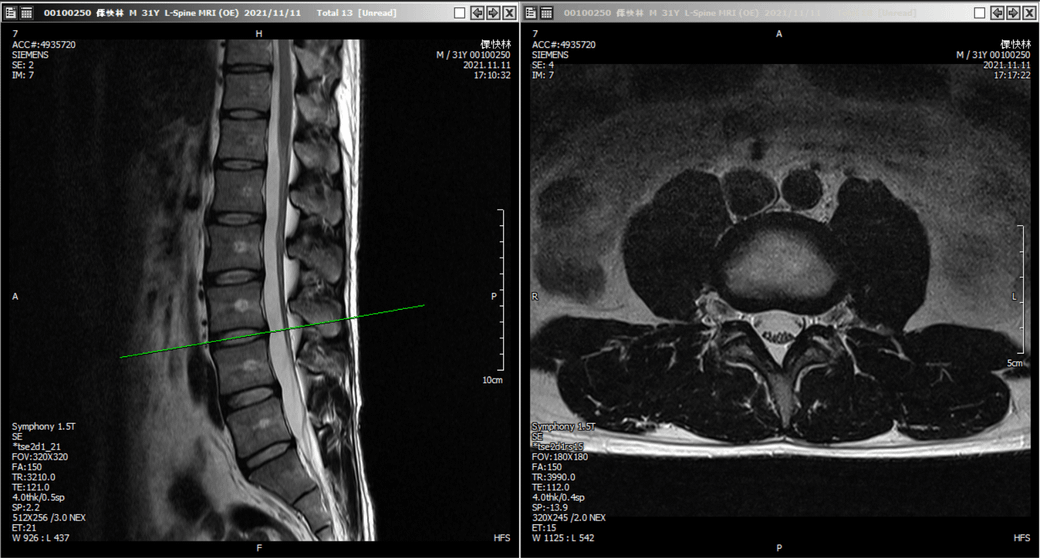

그런데 한 재활의학과에서는 아래 사진을 보고 근육 문제가 아닌 디스크 문제일 가능성을 제기했습니다. 3,4번인가 4,5번 쪽에 약간 디스크가 있긴 한것 같다고 하더라구요..

• 1번 째 사진

• 2번 째 사진

일반적으로 신경성 파행의 경우 허리를 숙이는 동작을 통해 증상이 완화되고 허리를 곧추세우면 통증이 악화되는 양상을 보입니다. 그러므로 사진상에서도 그렇지만 임상적으로도 움직임에 따라 증상이 악화되고 허리를 숙일 경우 통증이 더 악화되므로 척추 협착증이나 디스크를 의심하기에는 잘 맞지 않는 부분이 있습니다.

제가 판단하기에는 MRI상 이야기 하시는 통증을 유발할만한 병변이 보이지 않습니다.